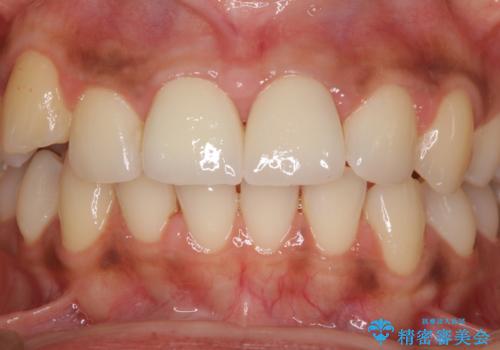

- 上の前歯2本の審美障害を気にして来院された患者様です。樹脂が無造作に充填されており、色合いも形態も不自然で、歯肉も腫れているため、オールセラミッククラウンにて補綴することとしました。

充填されたレジンを取り除いたところ、歯肉の炎症による出血が認められました。セラミッククラウン装着後は歯肉が腫れることもなく、仕上がりも自然な歯のようになり、患者様には大変満足していただきました。